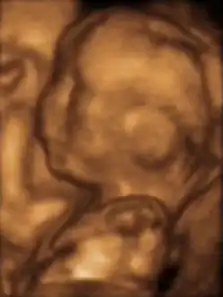

- определение плода и плаценты с помощью ультразвуковой диагностики.

Пренатальная диагностика

Прената́льная диагно́стика — дородовая диагностика патологий развития — проводится в несколько этапов. В период между 10-й и 13-й неделями проводятся пренатальный скрининг риска синдрома Дауна и синдрома Эдвардса по УЗИ и биохимическим маркерам. Период между 16-й и 18-й неделями считается оптимальными сроком для проведения так называемого тройного биохимического скрининга синдрома Дауна, синдрома Эдвардса и дефектов нервной трубки. Тройной скрининг может проводиться с 14-й по 20-ю недели.

На 20−24-й неделе проводится повторное УЗИ для определения состояния плода по органам.

На 30−34-й неделе проводится третье УЗИ для определения состояния плода и плаценты.

- Трёхмерное УЗИ 12-недельного плода